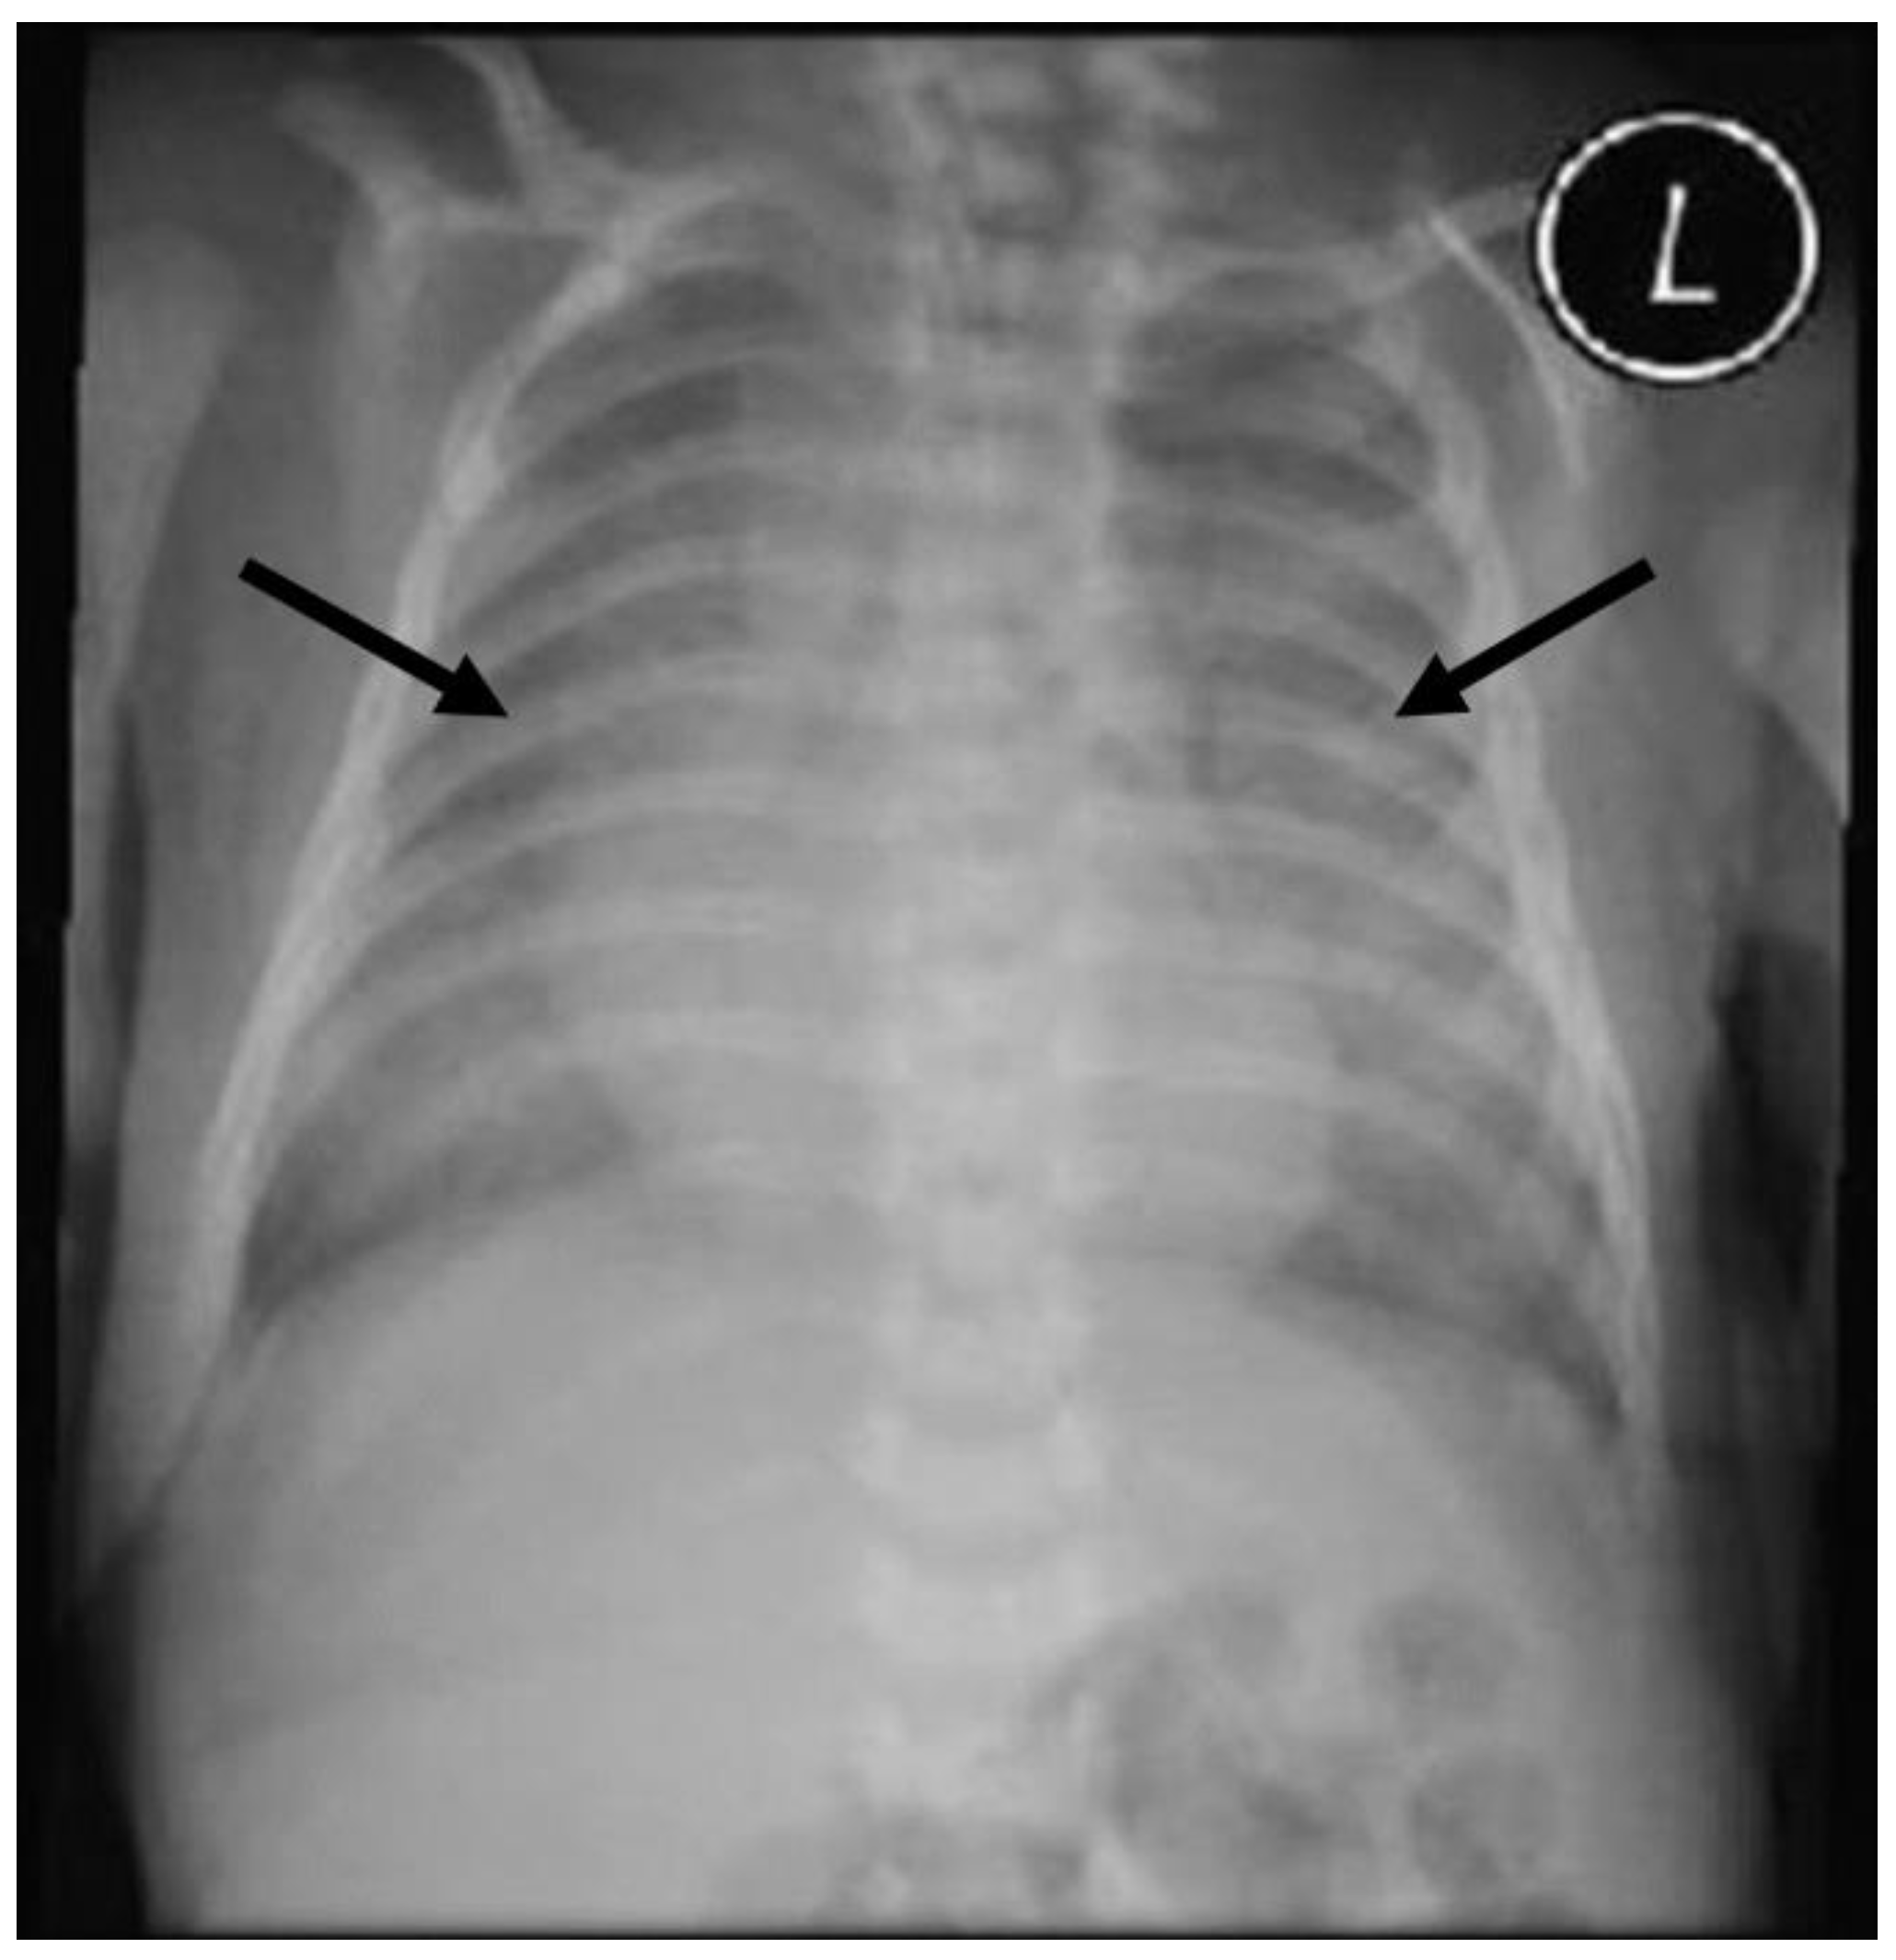

2. Case Presentation